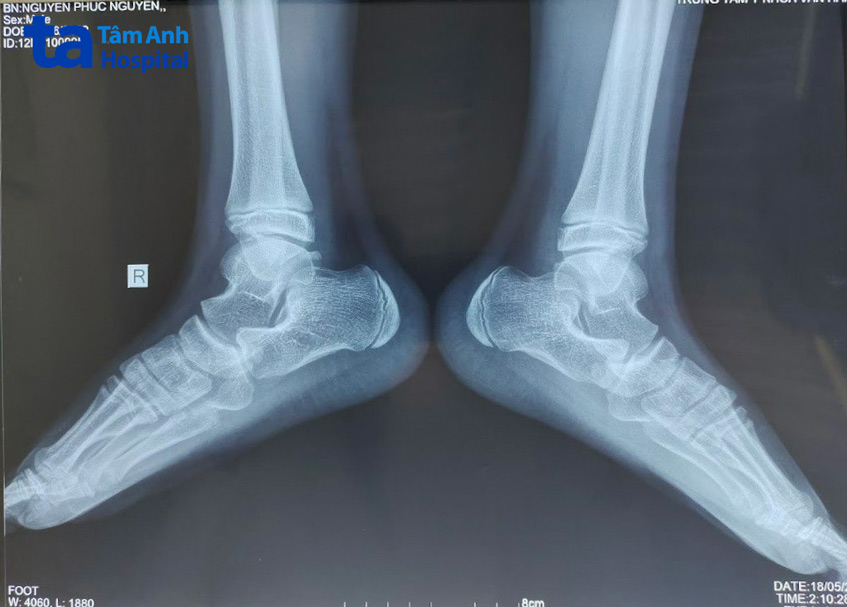

BS.CKI Nguyễn Văn Ơn chia sẻ, thăm khám lâm sàng và các kết quả chẩn đoán hình ảnh cho thấy vòm bàn chân của bệnh nhi vô cùng thấp, gần như phẳng hoàn toàn. Tình trạng này thường chỉ xảy ra ở trẻ dưới 2 tuổi, sau đó, vòm bàn chân sẽ dần hình thành cùng với hệ thống dây chằng. Tuy nhiên, một số trẻ lớn hơn 2 tuổi, lòng bàn chân vẫn bằng phẳng, không lõm vào, gây ra hội chứng bàn chân bẹt. Hội chứng này làm cơ và dây chằng bị căng quá mức trong thời gian dài, gây đau nhức; các xương ở cẳng chân xoay khi đi lại, chạy nhảy, làm khớp gối bị xoay lệch, dẫn tới đau và viêm, thậm chí là thoái hóa khớp gối sớm; dáng đi của trẻ thay đổi, ảnh hưởng tới nhiều bộ phận khác trên cơ thể như mắt cá chân, đầu gối, bắp chân, hông, thắt lưng, cẳng chân… Về lâu dài, tình trạng này sẽ gây tổn thương khớp gối, khớp háng và cả cột sống.

Tình trạng bàn chân bẹt ở trẻ em thường được điều trị bảo tồn. Tuy nhiên, cách này chỉ hiệu quả cho trẻ dưới 7 tuổi, do đó, phương pháp điều trị tối ưu dành cho bệnh nhi Phúc Nguyên là phẫu thuật can thiệp. Các bác sĩ mở một đường nhỏ khoảng 1 – 1,5 cm ở cạnh ngoài của bàn chân, sau đó bắt vít vào để nâng vòm bàn chân lên và bó bột nhằm giữ ổn định độ cong của bàn chân. Phương pháp điều trị này hoàn toàn không làm tổn thương hệ thống cơ, gân… của bệnh nhi. Nhờ đó, người bệnh ít đau, ít mất máu, giảm nguy cơ nhiễm trùng và phục hồi nhanh hơn.